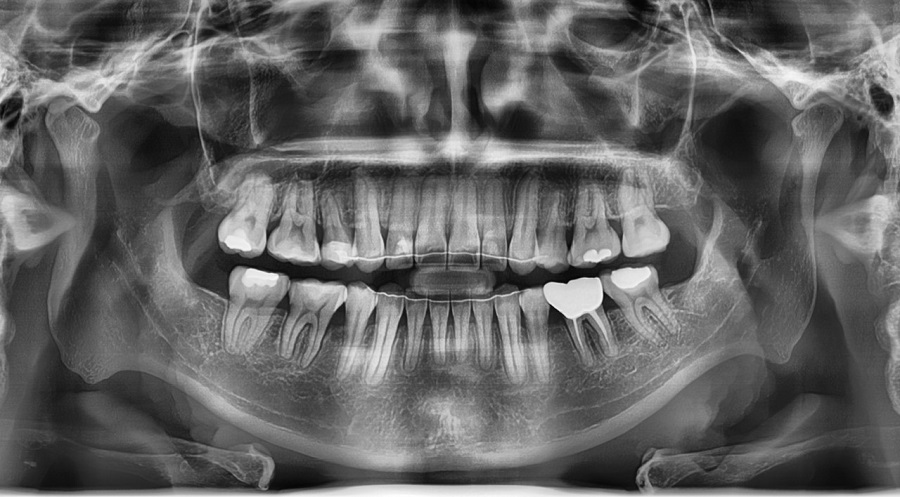

• 상악 우측 제2소구치 : 신경치료 후 크라운 수복을 미루다가 치아 파절

• 상악 좌측 제2소구치 결손 → 좌측 상악 대구치들의 전방이동

• 상악 양측 견치 공간 부족 → 높은 위치(High Canine)

• 하악 제2소구치 양측 모두 심한 설측경사

→ 그 공간으로 제1대구치가 전방 쓰러져 제2소구치의 공간이 거의 없는 상태

② 발치 결정 — 파절된 치아를 대신 발치

원래는2급 부정교합에서 발치 교정 시 상악 제1소구치를 발치하는 것이 일반적입니다.

하지만 이 케이스에서는 제2소구치가 치관이 파절된 상태였기 때문에

상태가 더 불량한 제2소구치를 치료적 발치로 대체했습니다.

③ 미니스크류 기반 후방이동 — 이 케이스의 핵심 단계

● 상악 좌측 구치부

상악 좌측 제2소구치 결손으로 인해 전방으로 이동해 있던 대구치를 원래 자리로 후방 이동해야 견치와 전치부 공간이 회복됩니다.

대구치를 후방이동 시키기 위해 미니스크류를 식립해 안정적인 고정원으로 삼았습니다.

● 하악 양측 구치부

특히 하악은 핵심 포인트가 있습니다.

• 제2소구치가 심하게 설측 경사

• 그 공간으로 대구치가 전방으로 쓰러져 있음(tipping)

• 일반적으로 미니스크류를 가장 많이 식립하는 위치인 interradicular(치근 사이) 스크류 식립보다는

특별하게 **retromolar pad(하악 구치 후방 부위)**에 미니스크류를 식립했습니다.

이 부위에 스크류를 심으면 후방 견인과 치아의 직립에 매우 효율적입니다.

✔ 하악 대구치 후방이동 + 직립 완료

전방으로 쓰러져 있던 하악 제1대구치가 완전히 직립되고 후방으로 이동한 덕분에,

이후 보철(크라운) 제작 시 치근 방향과 일치하는 형태로 제작 가능해졌습니다.

쓰러진 치아가 계속 교합압을 받는 경우 치아에 좋지 않은 영향을 줄 수 있으므로, 이러한 치아의 직립은 큰 의미가 있습니다.

✔ 상악 우측 제2소구치 발치공간 폐쇄와 상악 좌측 구치 후방이동을 통한 구치 관계 안정화